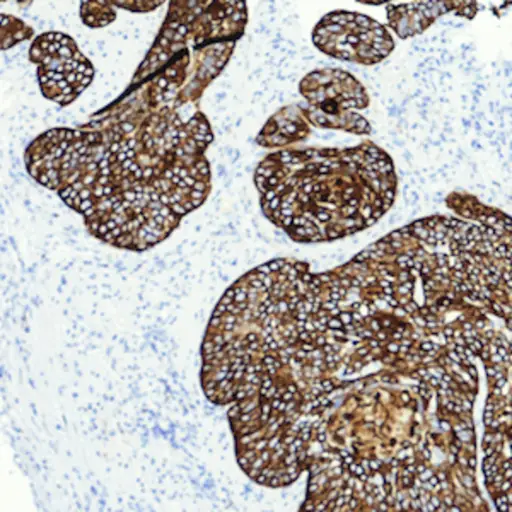

乳头状和扁平癌

乳头状癌是膀胱内衬在膀胱内衬上的肿瘤。它们从衬里朝向膀胱的中心生长。扁平癌,也称为无侵入性的扁平癌或平癌癌原位,是包含在膀胱内层的肿瘤。它们并不朝着膀胱的中心生长。